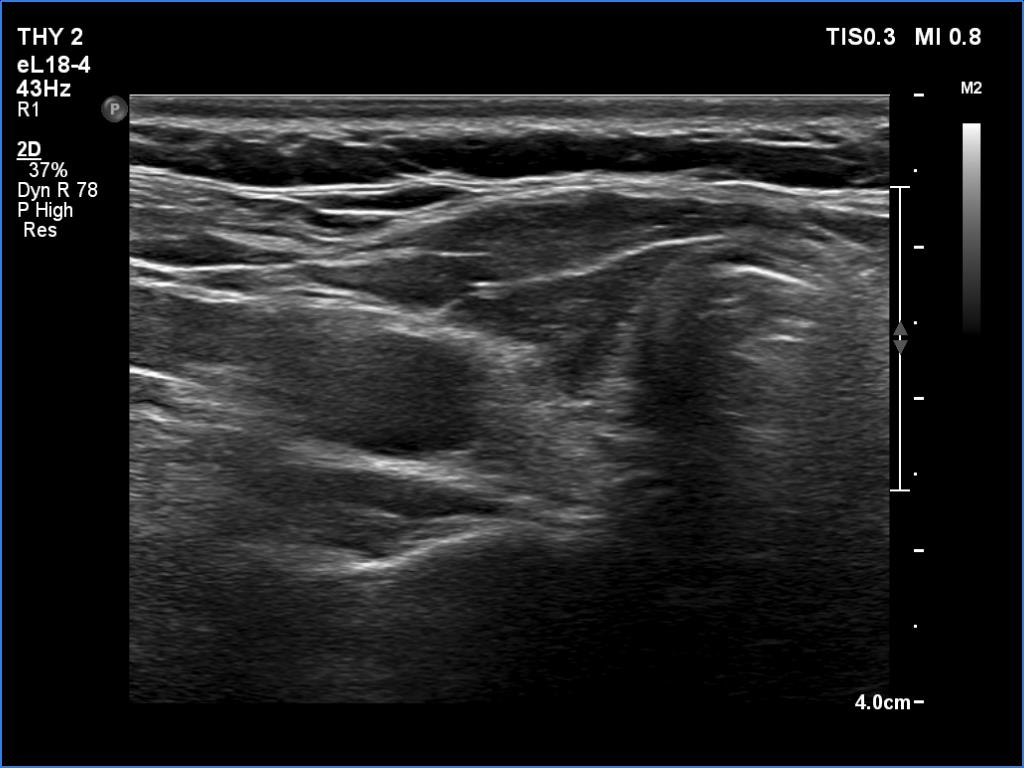

Ultrasonography. The thyroid was atrophic. Both lobes were composed of a central, larger hypoechoic area surrounded with echonormal tissue. The pattern did not correspond to nodule. The vascularity was decreased.

Comment. A central hypoechoic part surrounded with echonormal tissue is one of the typical presentations of Hashimoto's thyroiditis, not infrequently misinterpreted as a large hypoechoic nodule which occupies great part of a lobe. The irregular margins, the infiltrative borders of the thyroiditis are the main clues of differentiation this presentation from nodular goiter. The pattern can be observed usually in both lobes which is also characteristic of this form of thyroiditis.